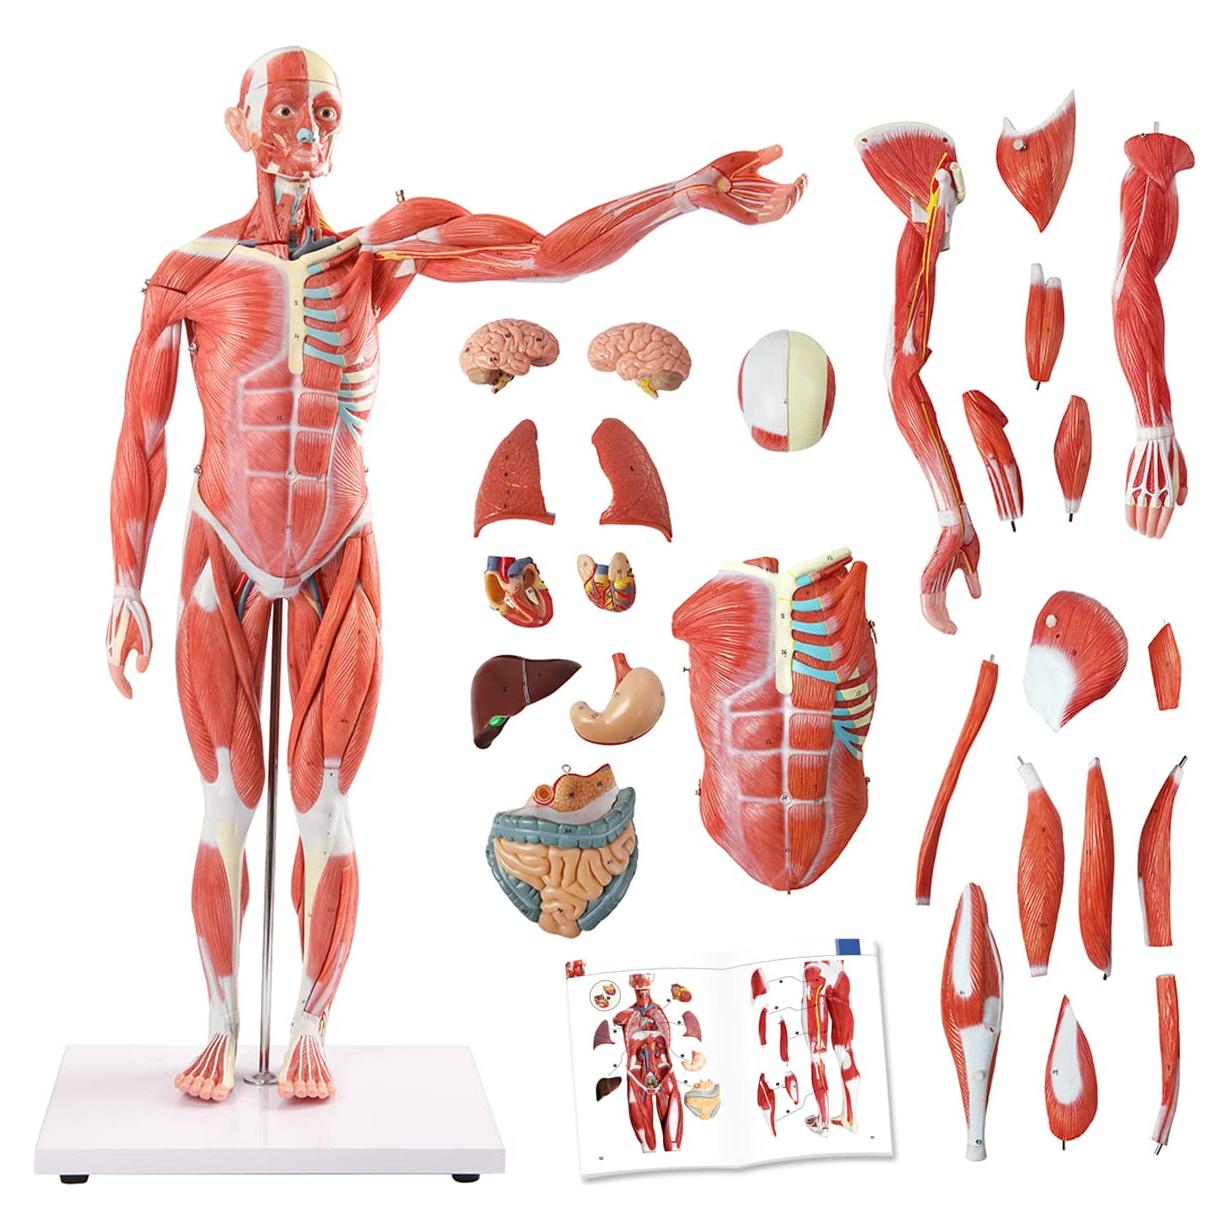

Modelos Anatómicos de Órganos marca Evotech (20 productos)

Modelos Anatómicos 3D EVOTECH SCIENTIFIC - Cuerpo, Corazón y Esqueleto